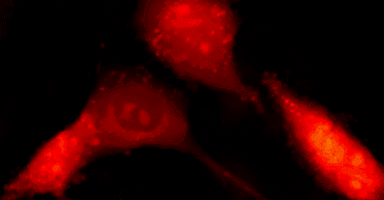

由于是动态三维形貌显微,可以做动态细胞筛选的,配合荧光模块做细胞分析 3D representation of a red blood cell.png Cell-Based-Assay-Cell-Migration.gif HeLa cells treated with Doxorubicin.gif 活体细胞四维成像.gif 酵母菌干重实时测量.gif |